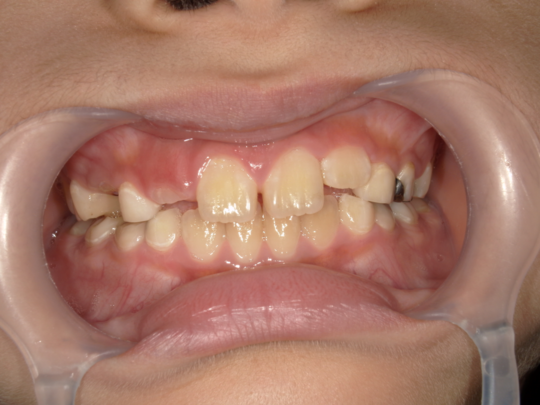

治療前

治療説明

歯科矯正で取り外し可能な矯正方法である床矯正とチンキャップで治療しました

治療期間 4年6か月

治療費用300000 円

治療後

治療の副作用(リスク)歯の動き方には個人差があり、予想された治療期間が延長する可能性があります。。床矯正の使用状況、矯正歯科治療には患者さんの協力が必要であり、それらが治療結果や治療期間に影響します。2次矯正が必要になる場合もあります。